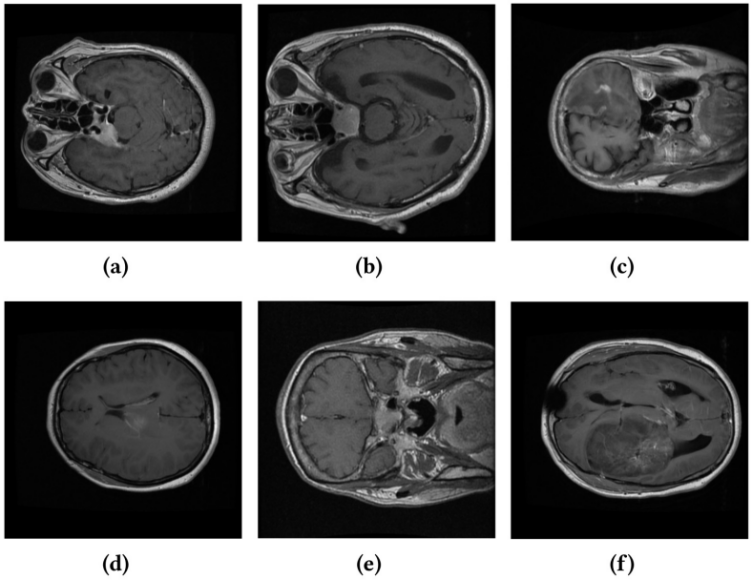

图 1 医学图像中的类间相似性与类内差异性示例